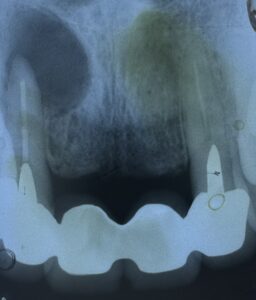

今時 珍しい 不完全な 根管充填。

歯根 の 先端に

大きな 膿疱 に よる

骨吸収 が 観られます。